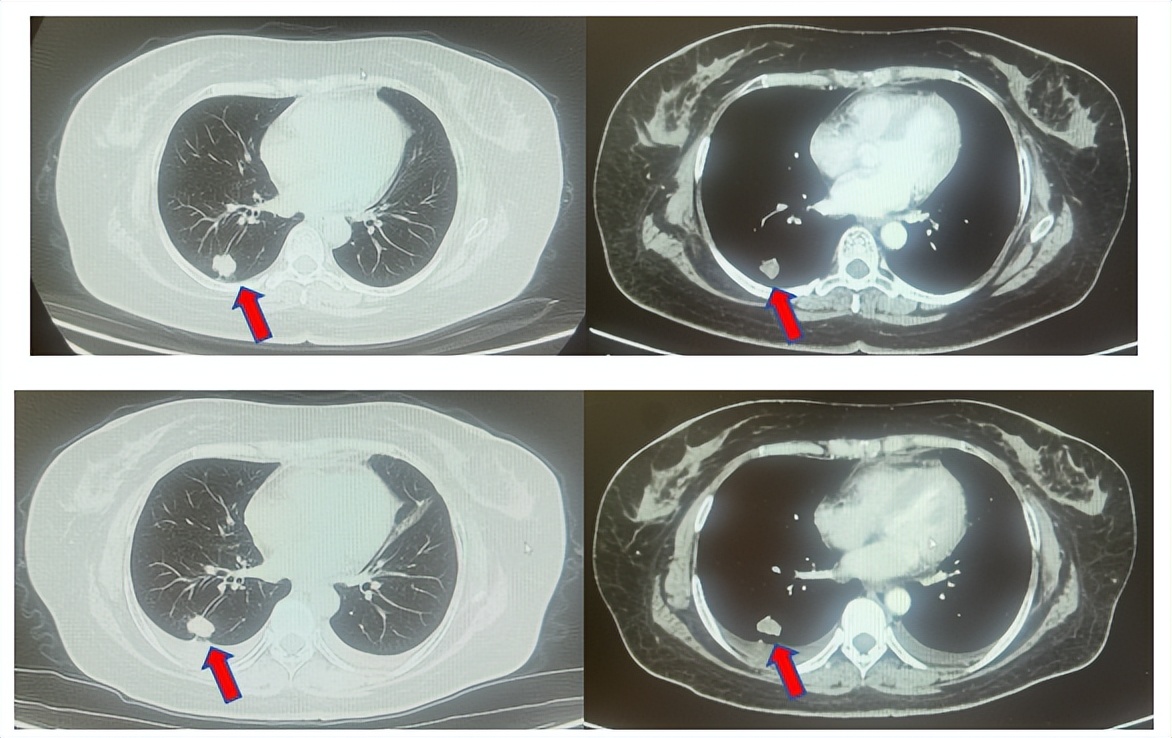

患者符合我科正在开展的“一项比较Durvalumab治疗与标准治疗(含铂化疗)用于PD-L1高表达晚期非小细胞肺癌患者一线治疗的III期随机、开放、多中心研究”的入组要求,经知情同意进入该试验,经随机进入化疗组,于2017年7月至2023年12月应用培美曲塞联合卡铂治疗6周期,后行培美曲塞单药维持治疗105周期,肺内CT现实右肺下叶病灶缩小90%,颅内病灶缩小100%,最佳疗效肺内病灶PR及颅内病灶达CR(图2),于2023年2月复查CT,肺内病灶逐渐增大,至2024年1月,疾病进展出组该临床试验,一线无进展生存为78个月。

图2:上两图分别展示2021年5月患者达到最佳疗效时肺CT肺窗及纵隔窗肺内病灶及肺门淋巴结影像,下三图表示最佳疗效时脑MRI影像

患者进入到二线治疗,该患者再次符合我科“优替德隆对照多西他赛治疗含铂化疗失败的局部晚期或转移性非小细胞肺癌的III期、开放、随机对照临床试验”经随机进入多西他赛组,截止至目前患者已行多西他赛治疗19周期,期间评效为SD(图3),二线无进展生存至今为14个月,患者总生存期截止目前超过92个月(整体治疗过程如图4所示)。

图3:上两图分别展示2024年1月患者一线进展时肺CT肺窗及纵隔窗肺内病灶影像,下两图表示2024年12月患者二线治疗间期评效时肺CT肺窗及纵隔窗肺内病灶影像